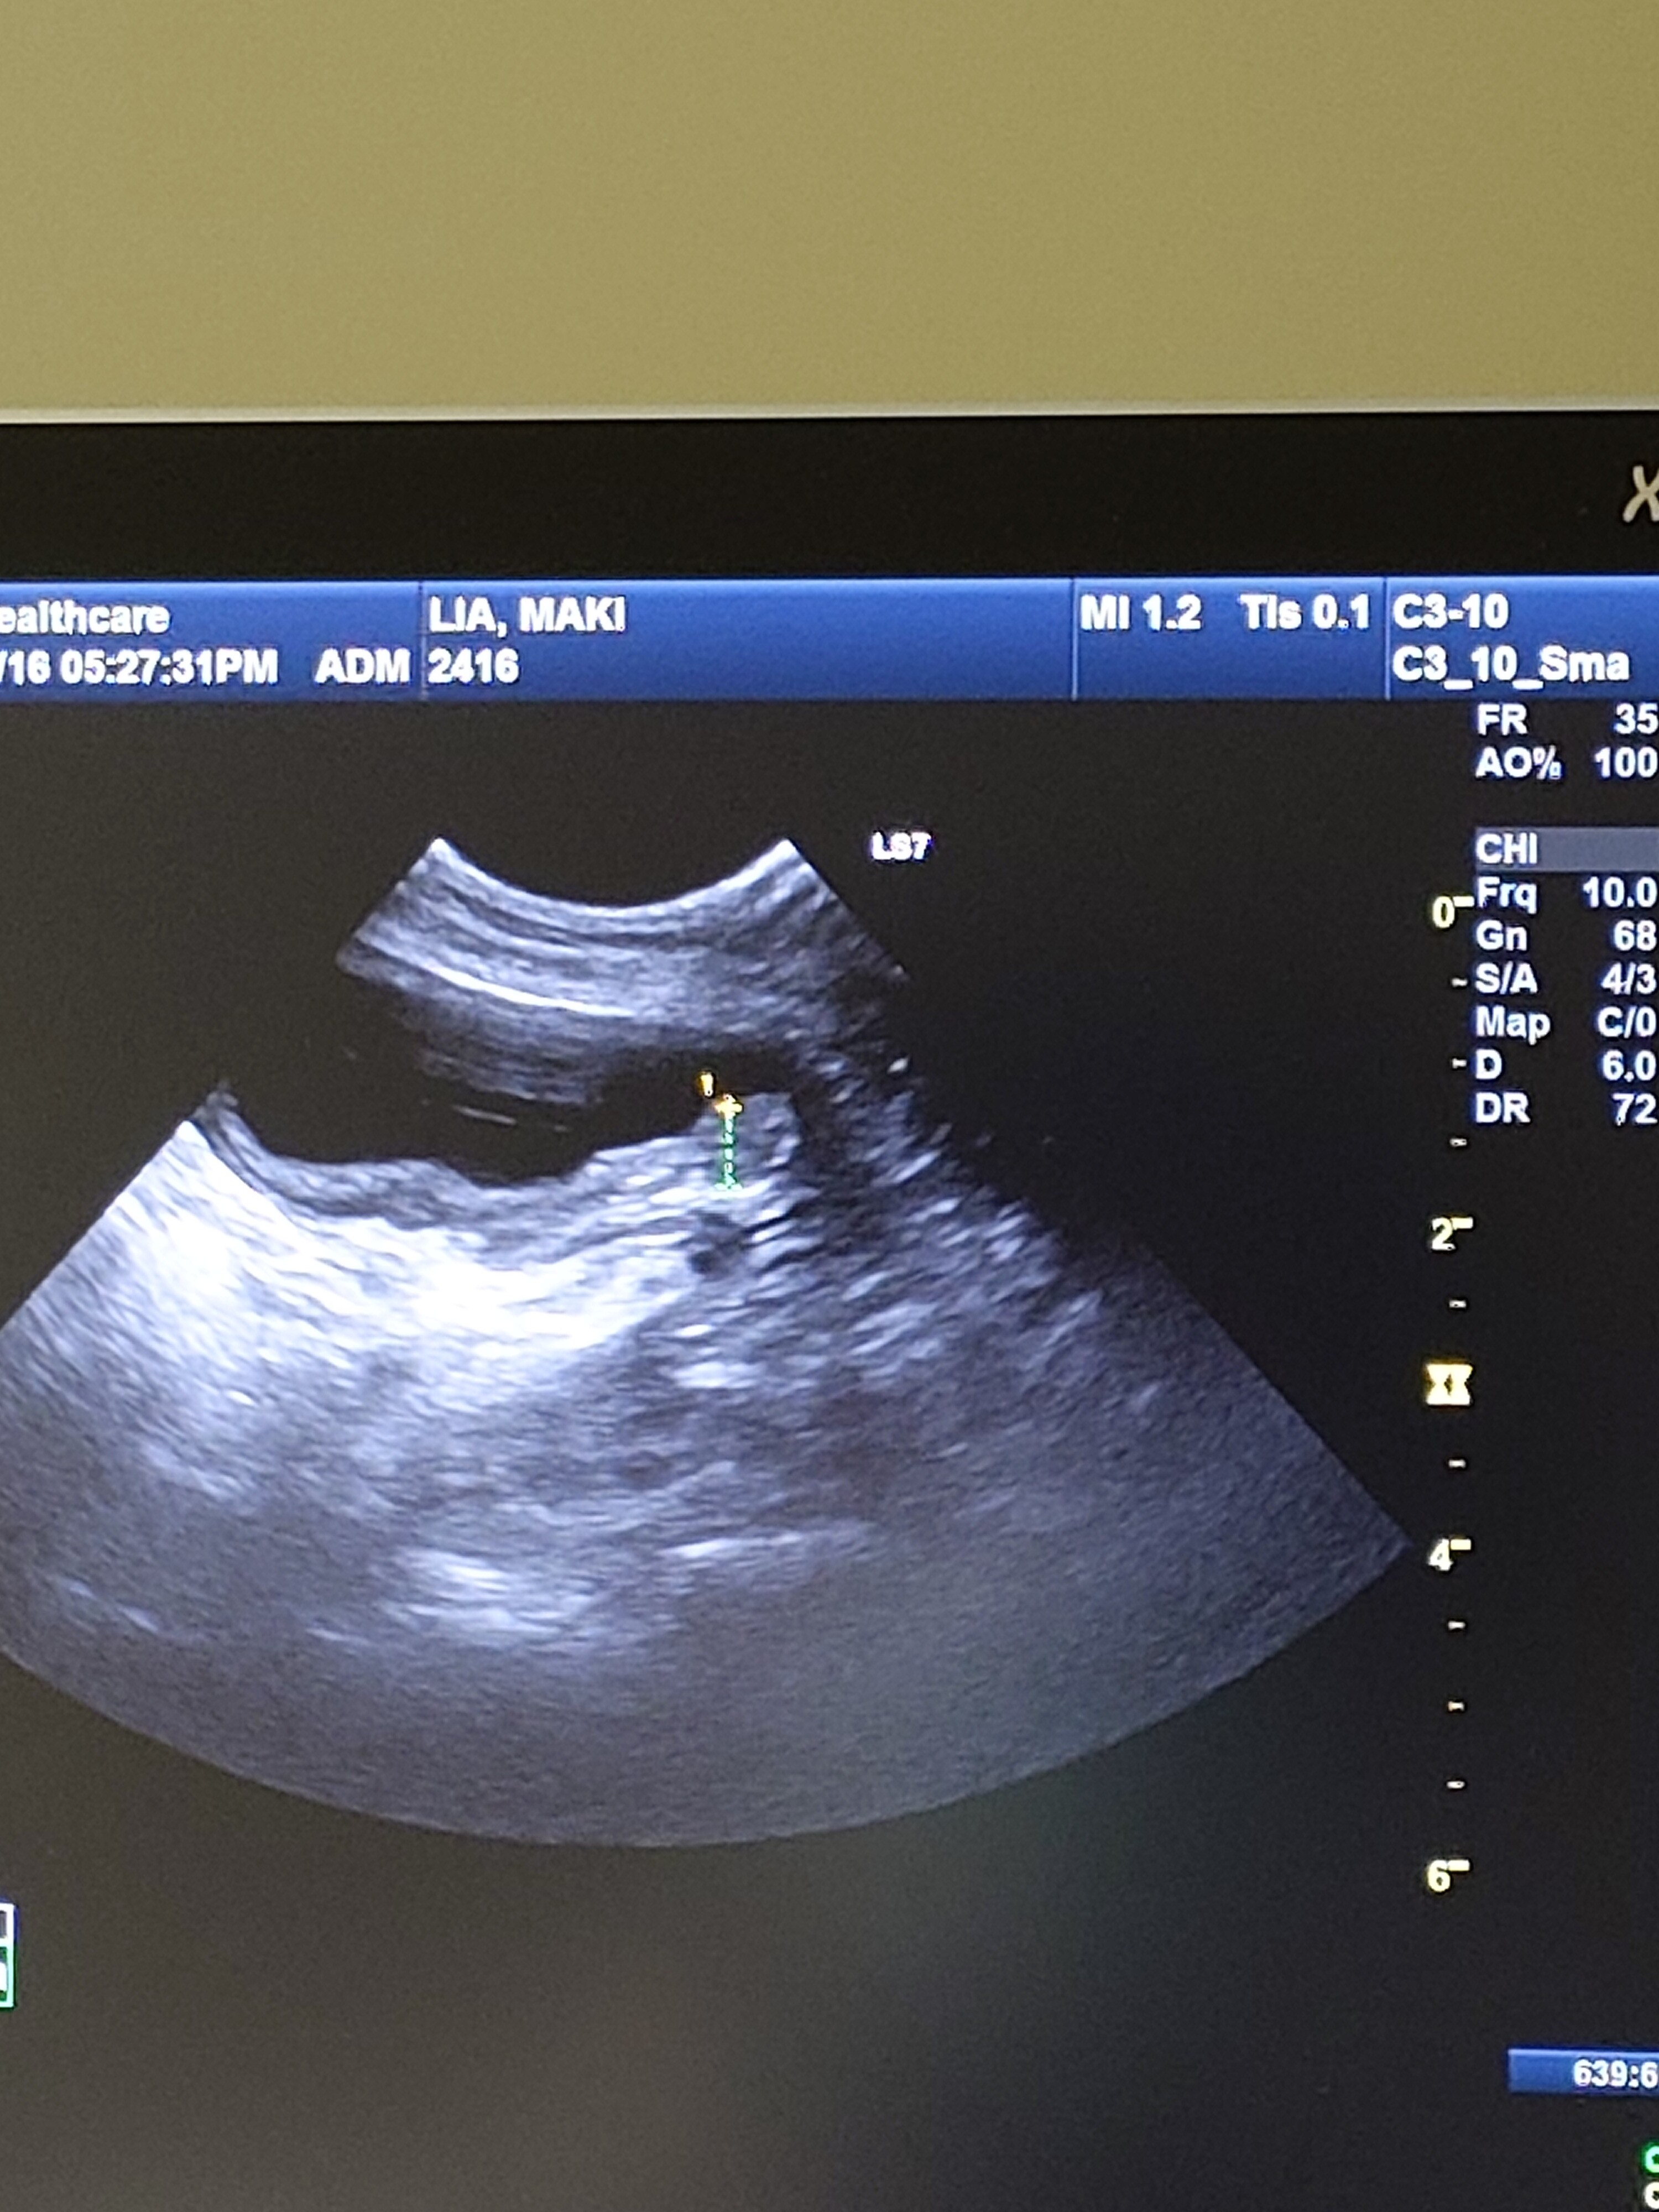

先日、1ケ月ぶりにエコー検査を。

すると、春程ではないけれど

再び腫瘍が大きくなっていました。